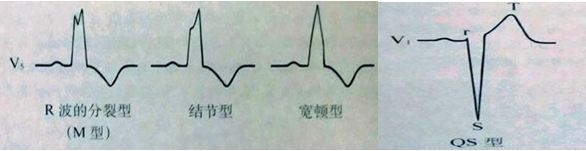

M波是指QRS波群程序“M”形态,主要见于右束支传导阻滞,V1和V2导联上出现“M”形表示右束支传导阻滞,这里的“M”形是指出现两个R波,QRS波群呈现rsR’、RSR’或rR’形态。而与V1、V2导联对应的V5、V6导联则会出现与之相对的类似导致的宽S波,具体见下图。

而判断束支传导阻滞是否完全,主要看QRS波群的时限,QRS波群>0.12s,就是完全性的,反之就是非完全性的。具体如下图。

(2)V5、V6导联上出现宽大R波,表示左束支传导阻滞,如宽大R波且切迹的”m”型和结节性,以及单纯宽钝的R波,而对应的V1、V2导联可见大S波,具体如下图。

图13